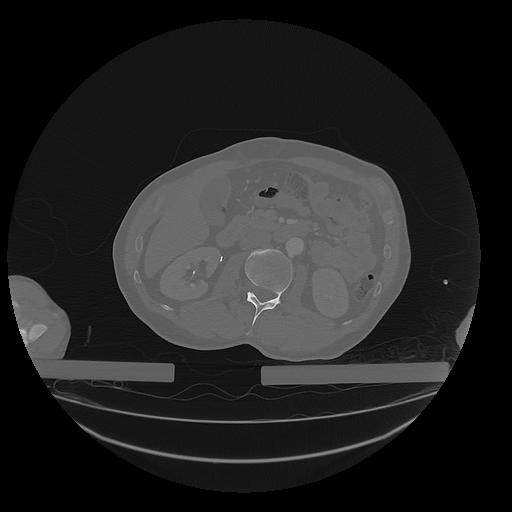

31 PULMON,CE,Vol,1.0,PULMON,,